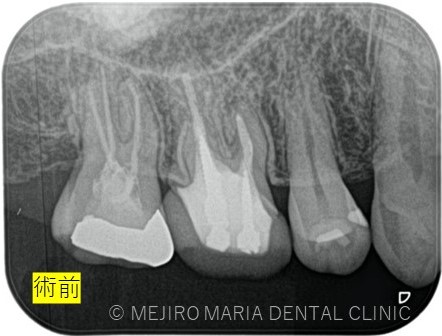

数週間前より右上がうずく感じがすることを主訴に来院された患者様です。近隣の歯科医院でも相談はしたが、特に問題がないと言い渡され、症状が気になり当院を受診されました。

右上7番には臨床症状(叩くことでの痛み)が確認できるものの、レントゲン上には根尖性歯周炎と判断できる透過像(病変の影)は確認できませんでした。歯科用CTを撮影してみると、近心根と遠心根に明らかな病変を認めました(歯科用CT画像1赤丸)。他の臨床症状と歯科用CT画像から右上7番の根尖性歯周炎と診断しました。